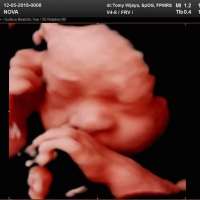

Nova quin